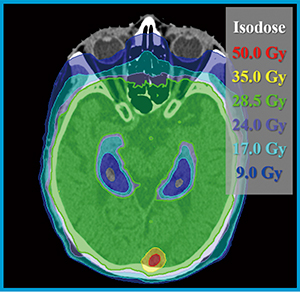

局所同時ブースト併用海馬抜き全脳照射への応用

図3 HyperArcを用いて計画された局所同時ブースト併用海馬抜き全脳照射の線量分布